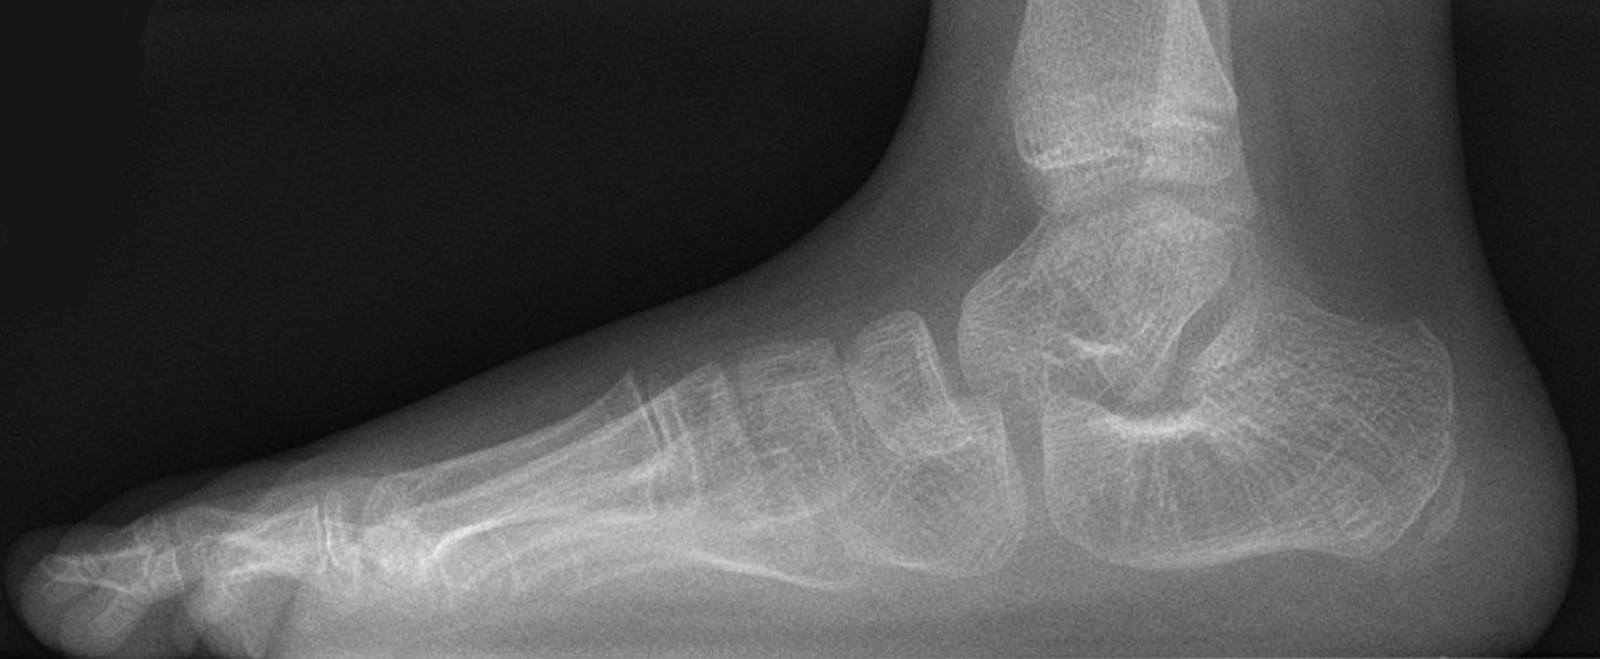

Radiologisch als een denkbeeldige as die door het midden van de talus wordt

getrokken, loodrecht op het gewrichtsvlak, niet uitkomt in het midden van het

eerste metatarsale bot van dig I. Normaal als de botten netjes in elkaars verlengde

staan hoort men een rechte lijn te kunnen trekken door metatarsale 1 en de tarsus.

| normale

voet (holle voet) |